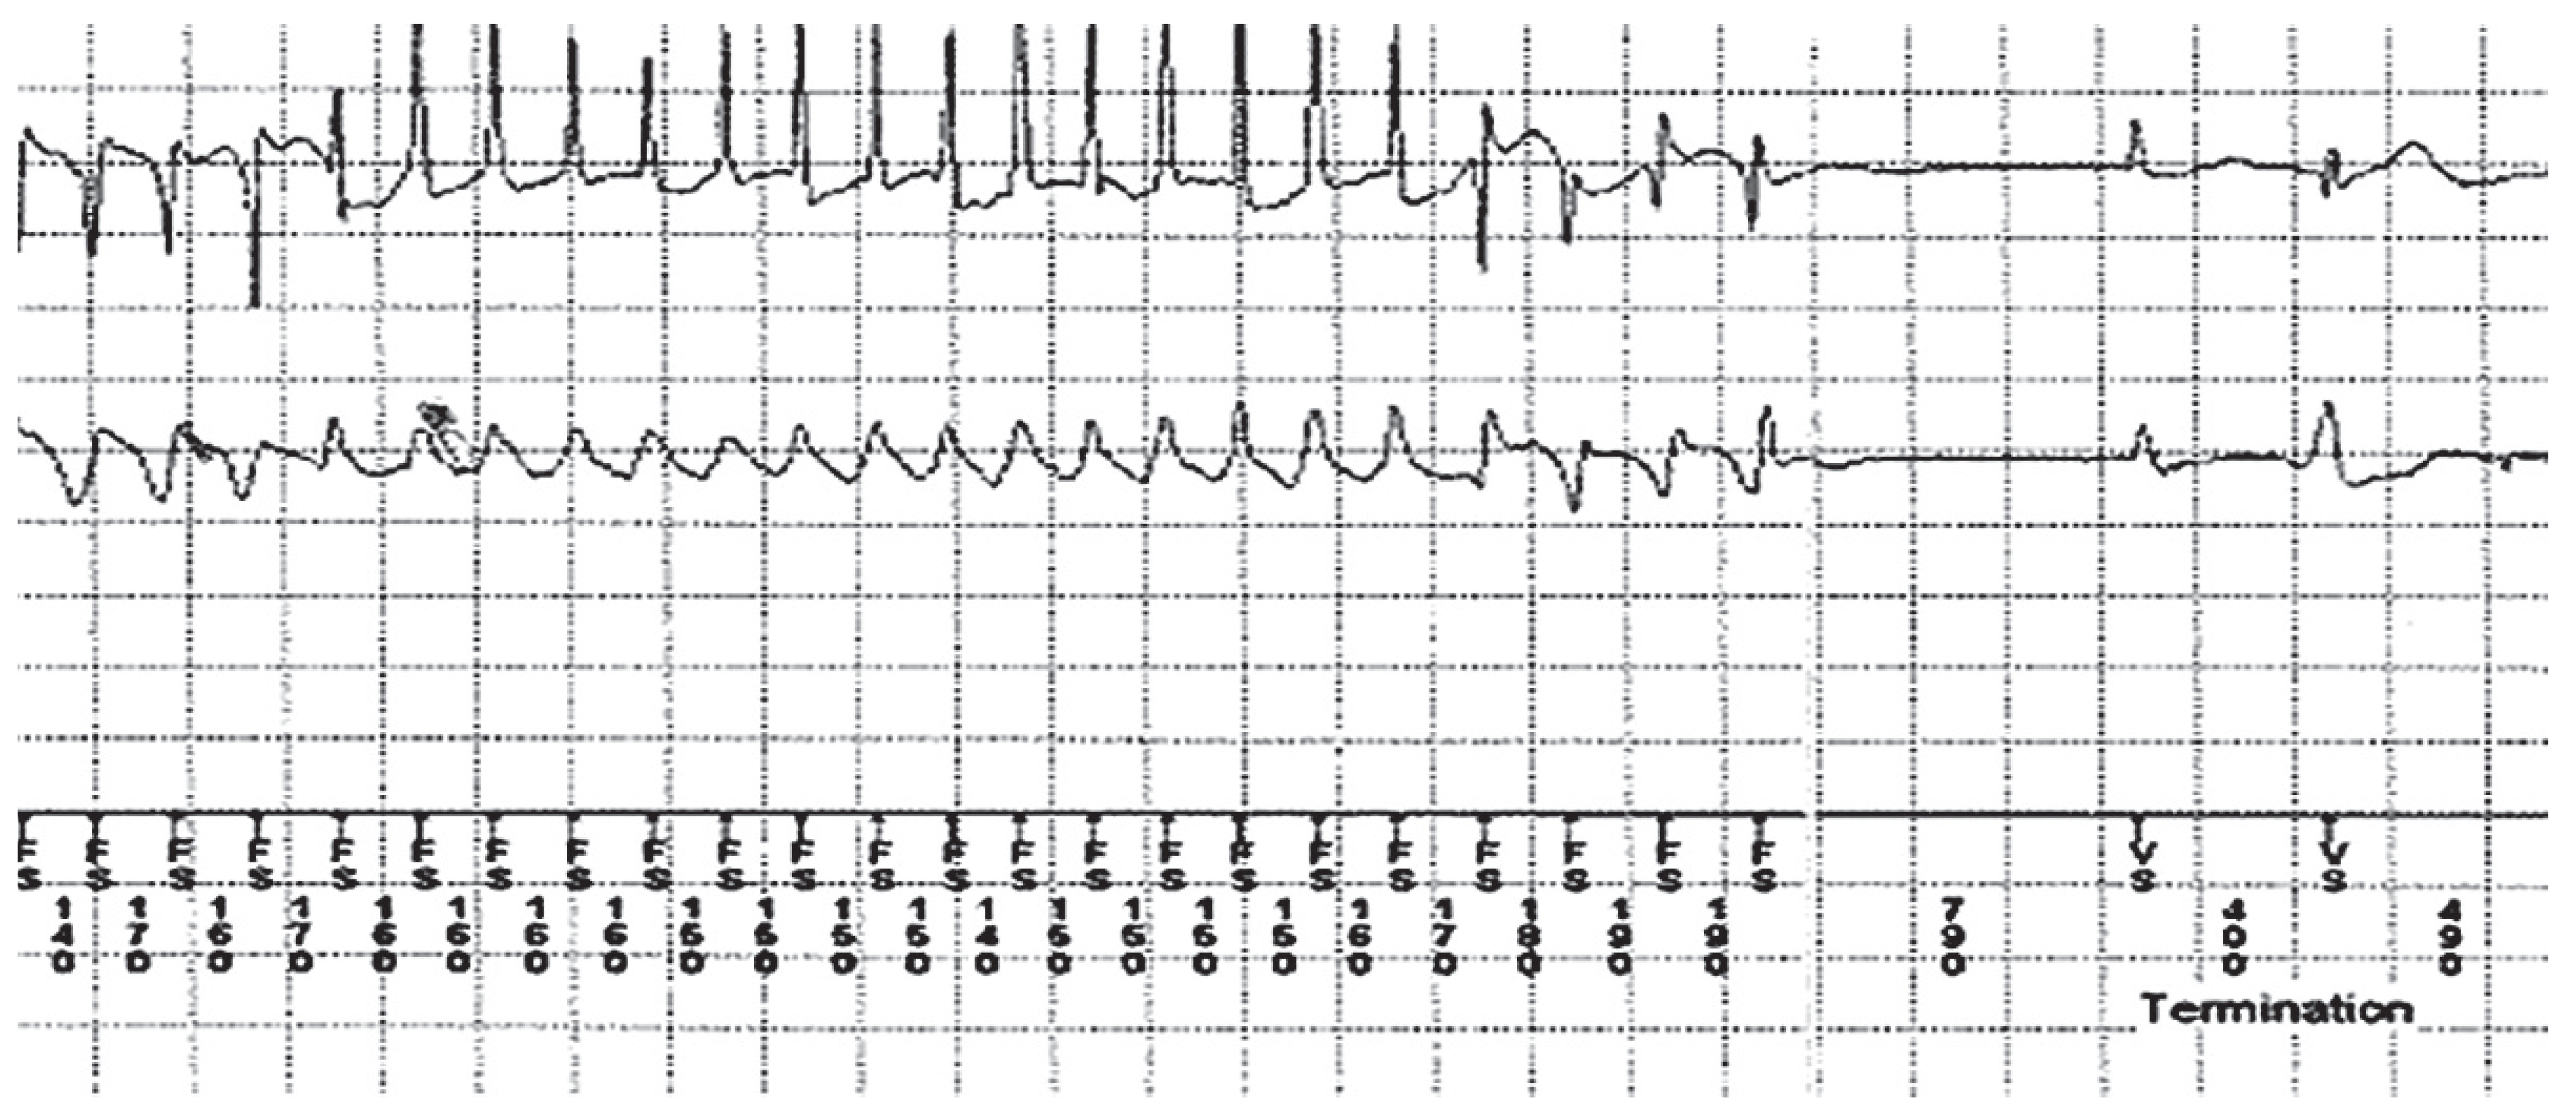

- Richter, S.; Gebauer, R.; Hindricks, G.; Brugada, P. A classic electrocardiographic manifestation of catecholaminergic polymorphic ventricular tachycardia. J Cardiovasc Electrophysiol. 2012, 23, 560. [Google Scholar] [CrossRef] [PubMed]